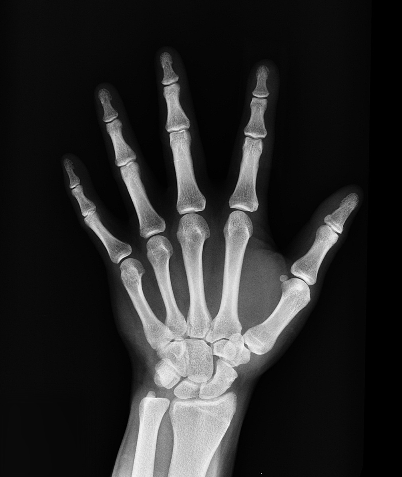

| 사고로 인한 임플란트 | O | 입증 서류, X-ray | 단순 노화는 제외 |

→ 진단서, 진료기록지, X-ray 등 추가서류가 필요할 수 있습니다. - 치과 실비는 무조건 안 되는 건가요?